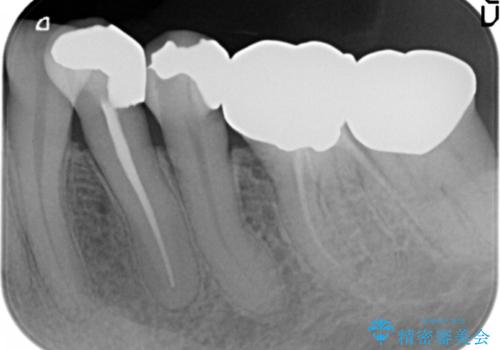

精査したところ、左下の小臼歯(左下5)の銀の詰め物の下に大きなう蝕を認めました。

またその手前の歯(左下4)は頬側転位していることを気にされておりました。

矯正をおすすめしましたが希望されず、最小限の方法で虫歯と歯並びを治したいとのことでした。

患者様のご希望により、セラミッククラウンにより可及的にう蝕除去後の補綴及び歯並びの改善を行いました。